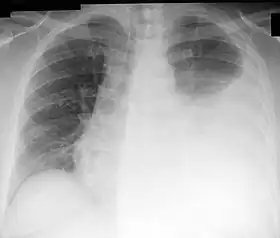

![]() Chest X-ray showing a left-sided pleural effusion (right side of image). This can be treated with thoracentesis. | |

Thoracentesis /ˌθɔːrəsɪnˈtiːsɪs/, also known as thoracocentesis (from Greek θώραξ (thōrax, GEN thōrakos) 'chest, thorax' and κέντησις (kentēsis) 'pricking, puncture'), pleural tap, needle thoracostomy, or needle decompression (often used term), is an invasive medical procedure to remove fluid or air from the pleural space for diagnostic or therapeutic purposes. A cannula, or hollow needle, is carefully introduced into the thorax, generally after administration of local anesthesia. The procedure was first performed by Morrill Wyman in 1850 and then described by Henry Ingersoll Bowditch in 1852.[1]